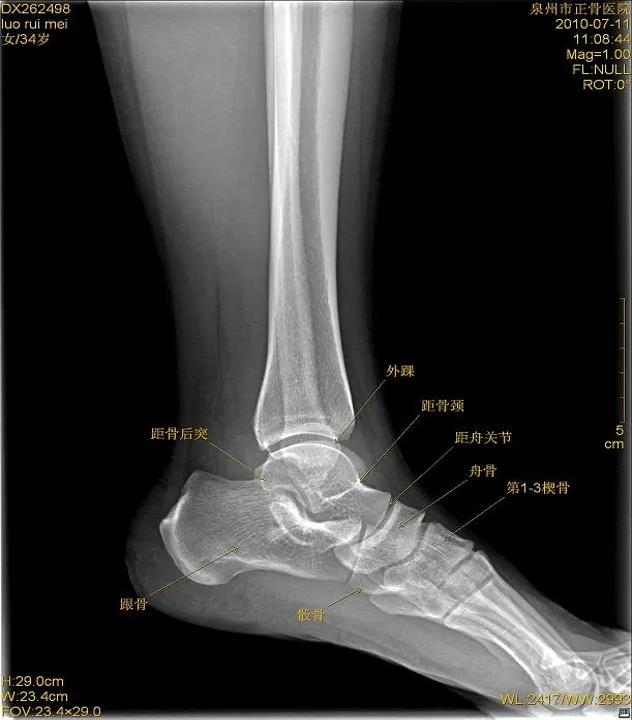

X线

踝关节侧位